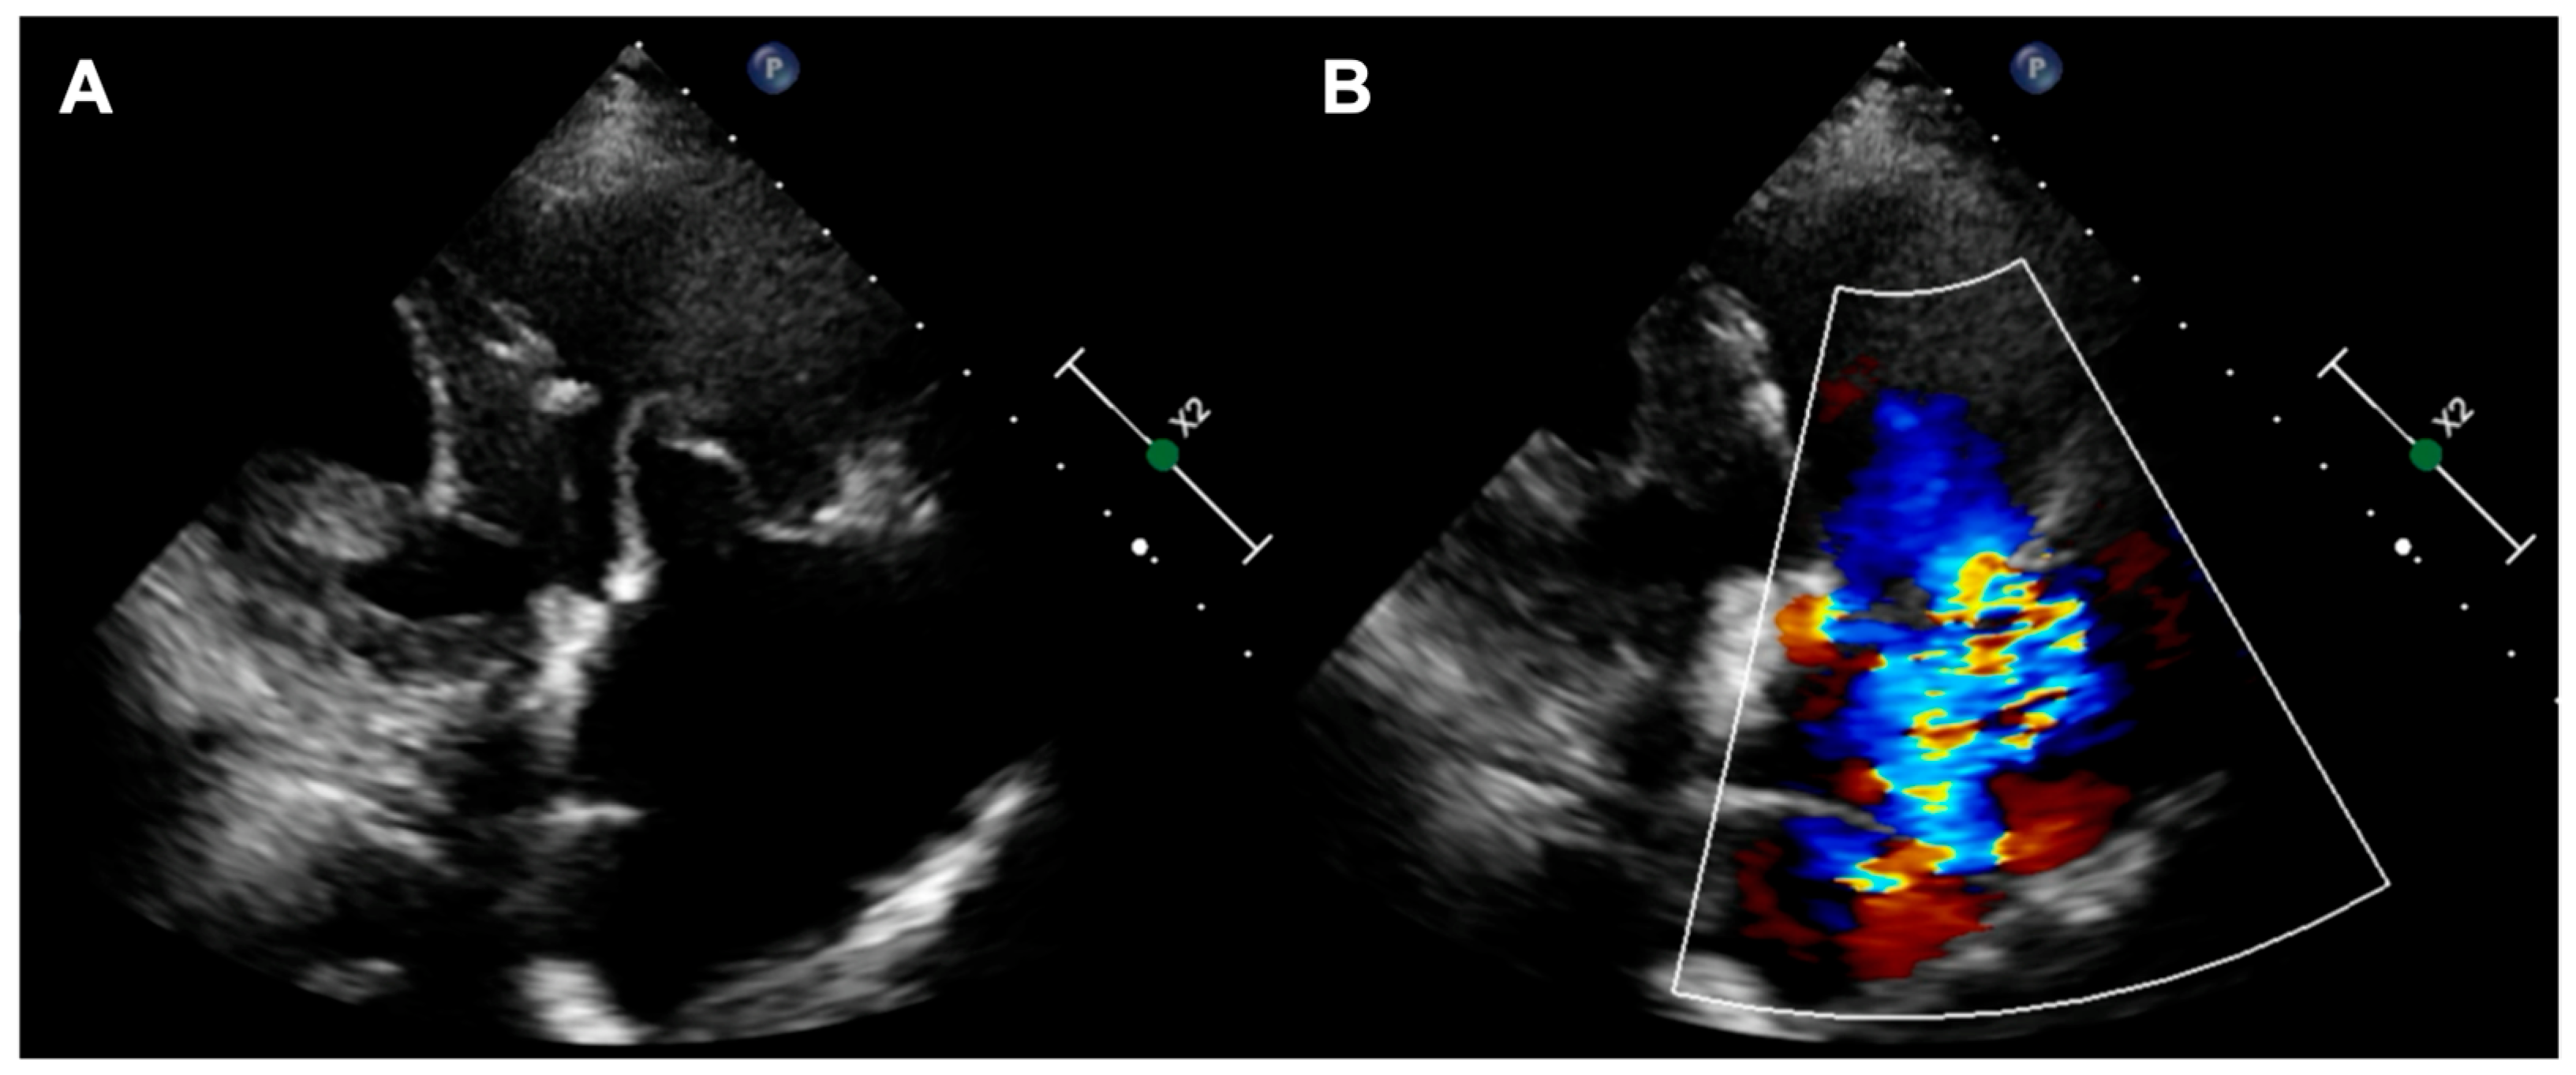

A 73-year-old woman with a history of two surgical interventions—an aortic valve replacement 25 years before and a thoracic aortic aneurysm repair 12 years before—was admitted to the hospital because of persistent heart failure symptoms in functional class NYHA III, accompanied by peripheral edema and ascites. The transthoracic echocardiography showed preserved function of the mechanical aortic prosthesis and torrential TR with tricuspid anulus enlargement. A further transesophageal examination revealed a large, mainly central coaptation deficit between the tricuspid leaflets, located mainly in the central region of the valve (Figure 3). Furthermore, a patent foramen ovale (PFO) with spontaneous right-to-left shunt was also diagnosed. Due to the valve anatomy, the patient was not deemed eligible for the transcatheter edge-to-edge repair. Because of the symptoms’ persistence, a two-step percutaneous procedure was planned. First, the PFO was closed with the 25 mm Amplazer occluder. Two weeks later, the CAVI procedure with the implantation of TricValve system valves (SVC 29 mm; IVC 45 mm) was carried out without complications. (Figure 4) We believed that the PFO closure was necessary before the CAVI procedure because the implantation of venae cavae valves in a patient with a patent PFO would have caused an exacerbation of the right-to-left shunt and possible patient desaturation. In observation, six and twelve months after the procedure, the patient remained on stable doses of oral diuretics and was considered to be in NYHA functional class II, without worsening heart failure or requiring hospitalization.

Figure 4. (A) Final angiographic result of TricValve implantation; (B) 3D view of IVC valve protruding to RA; (C) inflow from IVC through the implanted valve. IVC—inferior vena cava; RA—right atrium.